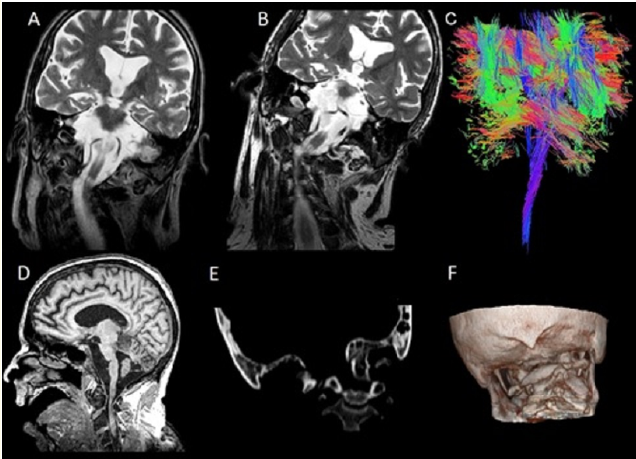

MRI Tractography Revealed an Unusual Brainstem Twisting in a Patient who Survived a Severe Traumatic Upper Spinal Dislocation

Calixto Machado, Jesus Perez-Nellar, Rafael Rodríguez-Rojas, Mauricio Chinchilla, Yanin Machado, Arthur Schift and Phillip A DeFina. 14(12): 09-12.